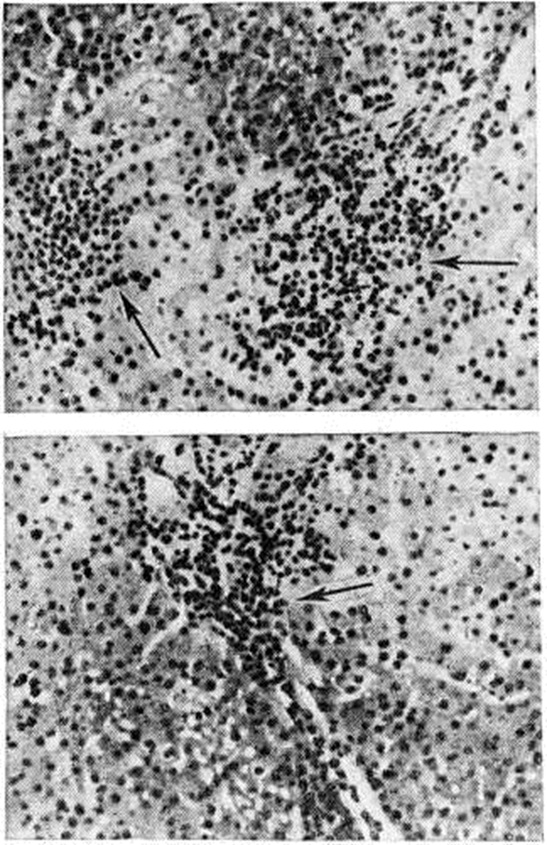

Рис. 5.

Микропрепарат печени при остром вирусном гепатите (пункционная биопсия): 1 — пролиферация звездчатых ретикулоэндотелиоцитов (купферовские клетки); 2 — митоз в звездчатых ретикулоэндотелиоцитах; 3 — коагуляционный некроз звездчатых ретикулоэндотелиоцитов (тельце Каунсилмена); 4 — митоз в гепатоците; 5 — коагуляционный некроз гепатоцита (тельце Каунсилмена); в остальных гепатоцитах начальные фазы развития баллонной (вакуольной) дистрофии; окраска гематоксилин-эозином; × 7 60.

Рис. 6.

Микропрепарат печени при остром вирусном гепатите (пункционная биопсия): прогрессирующее развитие диффузной острой баллонной дистрофии гепатоцитов (1); диффузная пролиферация звездчатых ретикулоэндотелиоцитов (2); митоз в гепатоците (3); окраска гематоксилинэозином; × 760.

Рис. 7.

Микропрепарат печени при остром вирусном гепатите (пункционная биопсия): очаг опустошения паренхимы на месте некроза в зоне периферического кровообращения ацинуса (указано стрелками) с воспалительным инфильтратом из полиморфно-ядерных лейкоцитов и лимфоидных элементов; окраска гематоксилинэозином; × 300.

Рис. 8.

Микропрепарат печени при остром вирусном гепатите (пункционная биопсия): обратное развитие дистрофических изменений гепатоцитов; формирование «поздних» узелков (указано стрелкой) с сохранившимся коагуляционным некрозом гепатоцитов (а) и без коагуляционного некроза гепатоцитов (б); окраска гематоксилин-эозином; × 760.

Рис. 9.

Микропрепарат печени при безжелтушной форме острого вирусного гепатита (пункционная биопсия): обильные инфильтраты (указаны стрелками) в области центральной вены дольки печени (верхний рисунок) и в области портального тракта (нижний рисунок); окраска гематоксилинэозином; × 300.